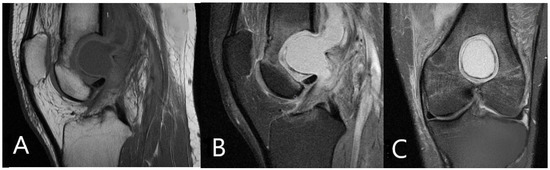

2. Materials and Methods

3. Management and Outcome